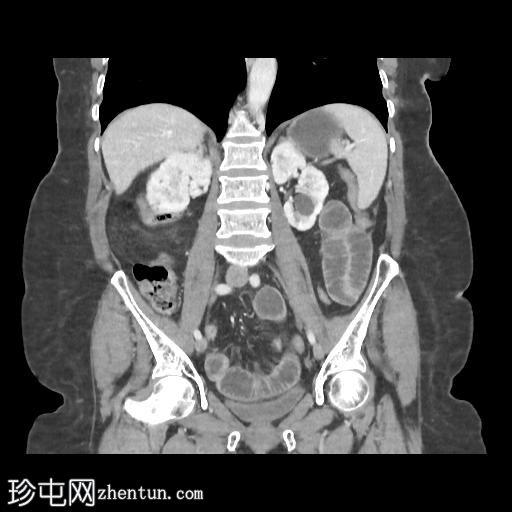

冠状位增强扫描(门静脉期)

胆囊缩小,囊壁增厚,提示慢性炎症改变。胆囊(底部)与十二指肠(球部)腔之间可见细小瘘管,胆囊内及肝内、肝外胆管内均可见气体(胆道积气)。

远端空肠内嵌顿一枚较大的胆结石(3.5 cm),近端空肠袢扩张,回肠袢、末端回肠及结肠均塌陷。

本病例符合典型的里格勒三联征:

异位胆结石

小肠梗阻

胆道积气